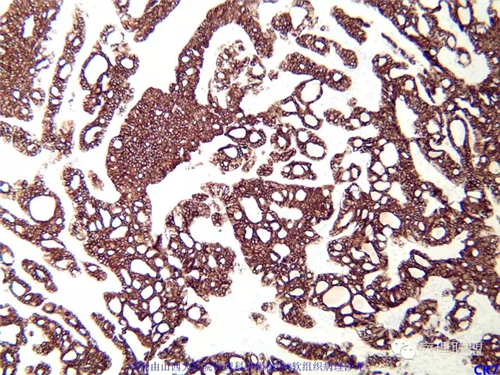

免疫组化结果阴性:S-100,SMA,Calponin,CD10,CD99,CD34,CEA,PHH3。

本例形态学上是非常典型的双相型滑膜肉瘤,滑膜肉瘤临床上大部分表现为生长缓慢的肿瘤。以青壮年多见,主要发生于四肢大关节附近,也可见于其他少见部位,如肺、肾等实质器官,形态学分为5种类型:单相纤维型、单相上皮型、双相型、低分化梭形细胞型和小细胞型。有文献报道个别患者有长达20年的病史。